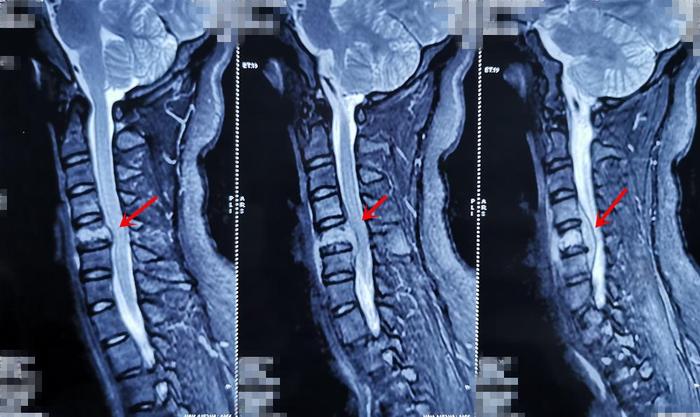

现病史:患者1年前在无明显诱因出现颈背部疼痛,呈间歇性发作,休息后可缓解,活动后加重。就诊于当地医院,行颈椎MRI检查,考虑颈椎嗜酸性肉芽肿可能,给予口服药物治疗,效果欠佳。约1个月前,患者自诉上述症状加重,并伴有左上肢放散痛,以上臂为主。门诊再次行颈椎MRI检查示,颈5椎体局部骨质破坏,颈4-6椎体左后方椎旁、椎管内脓肿形成;考虑结核可能性大。并影像学资料对比发现,颈5椎体骨质破坏较前加重伴椎管内脓肿、压迫神经脊髓。

术前影像学资料: